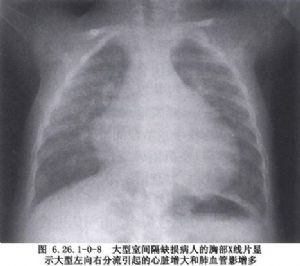

室間隔缺損的大小變異很大,按其口徑臨牀上大致可分爲大、中、小三型。大型室間隔缺損的口徑可以相當於或稍小於主動脈開口,因此右室壓力可接近於體循環壓力。中型室間隔缺損,又稱“限制性”室間隔缺損,其口徑約爲主動脈口徑的1/3~2/3,這類缺損可造成右室收縮壓升高,有的可高達左室收縮壓的50%,兩心室間有壓力階差存在;肺循環和體循環血流量比值上升到2~3.5倍。小型室間隔缺損,是指口徑小於主動脈口徑的1/3,右室收縮壓一般無明顯升高,肺循環和體循環血流量比值<1.75(圖6.26.1-0-8~6.26.1-0-12)。